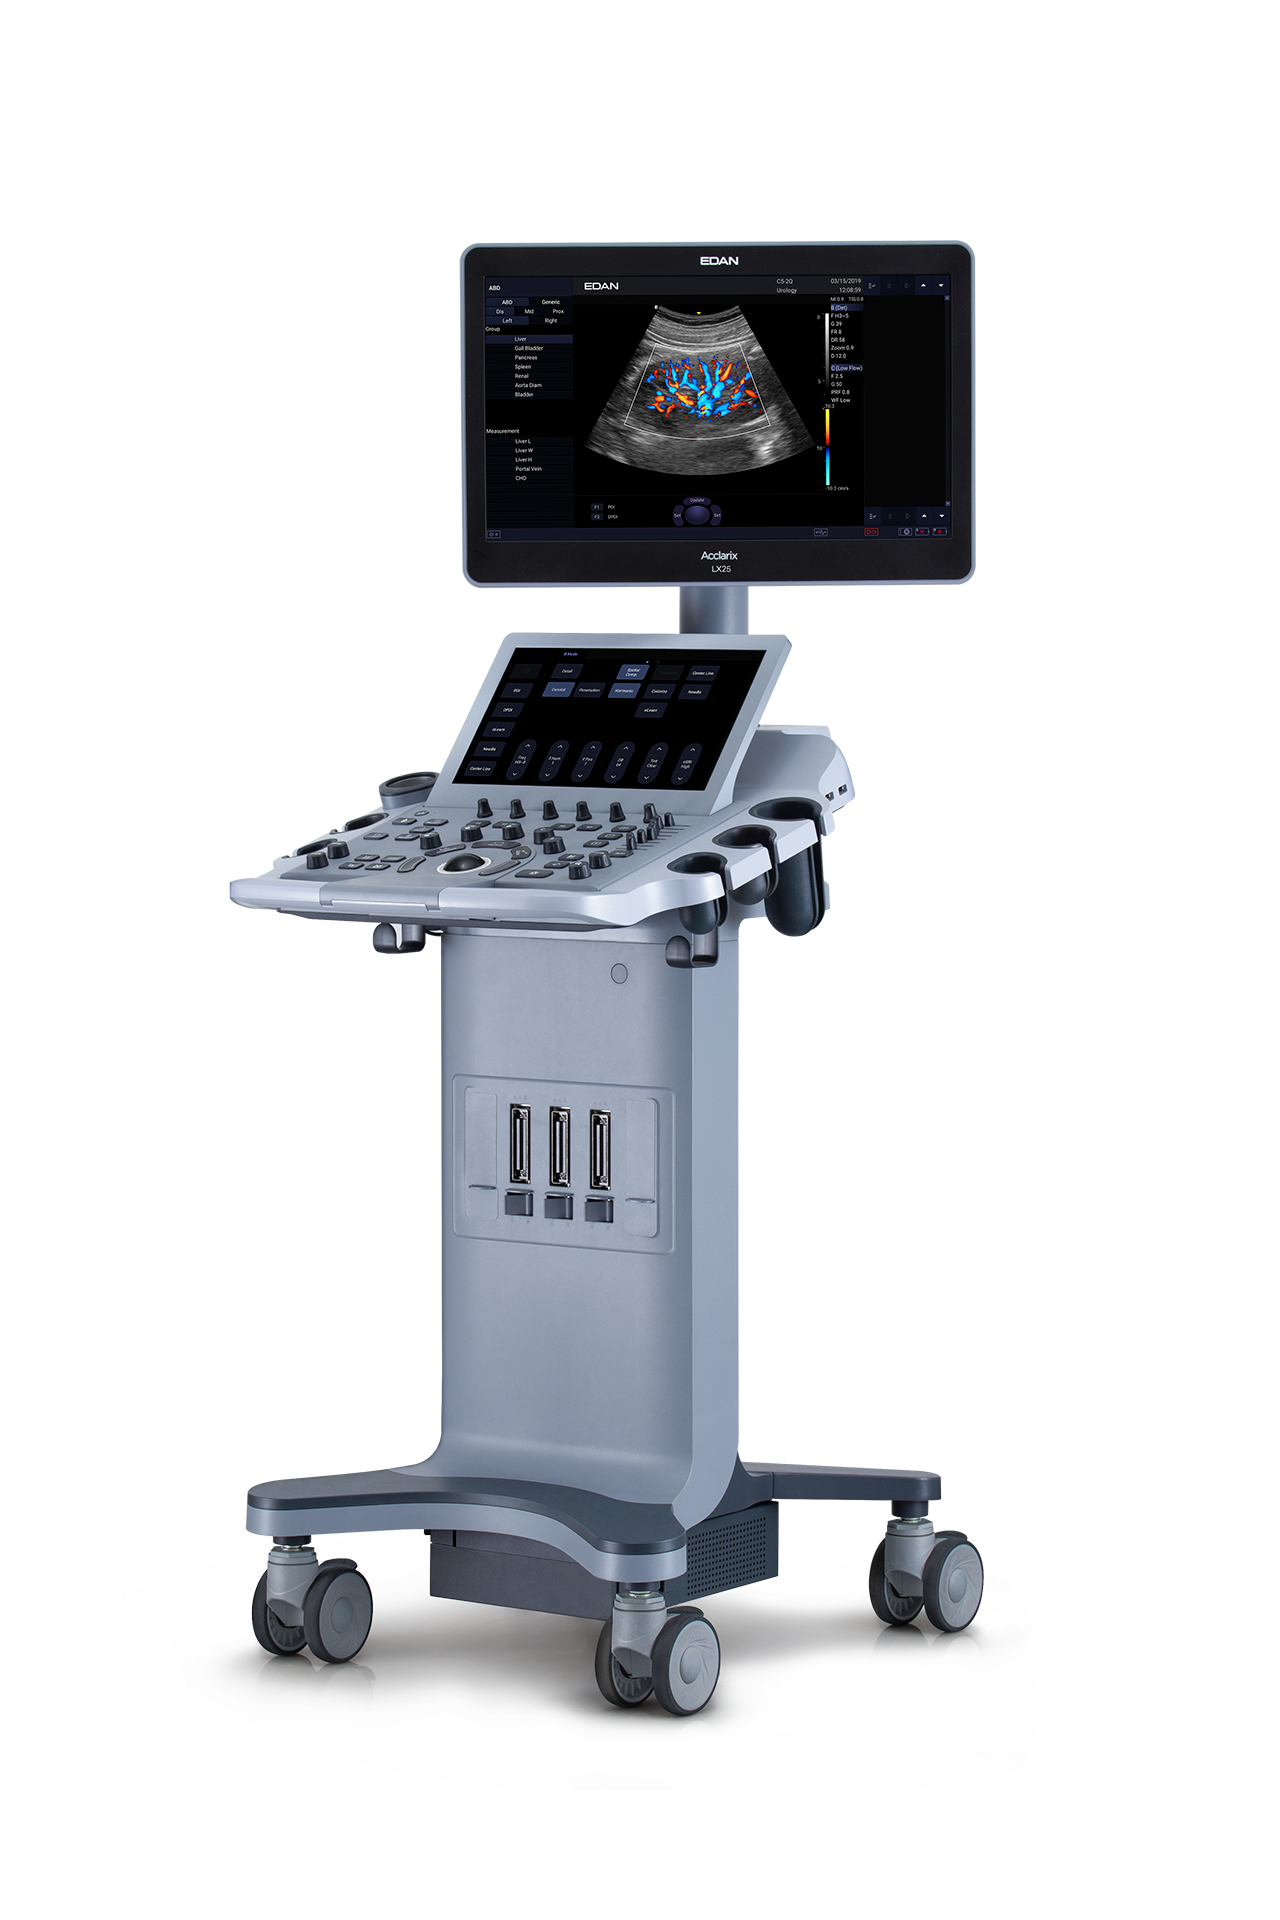

Ecógrafo Estacionario EDAN Acclarix LX25

Ecógrafo Estacionario EDAN Acclarix LX25

- Monitor LCD de 21.5″ HD con ángulo de visión multidimensional.

- Pantalla táctil de alta sensibilidad de 14″ que permite un funcionamiento eficaz.

- Diseño de calentador de gel.

- Configuración de 3 puertos para transductores.

- Diseño de ajuste de altura ergonómico.

- Baterías de respaldo y tiempo 2h de exploración continua.

Gracias a la innovadora tecnologia EDAN TAI, ya las múltiples tecnologías de procesamiento de

imágenes, Acclarix LX25 puede mostrar perfectamente la imágen de ultrasonido en diferentes

modos. ayudando al ecografista a realizar un diagnostico más preciso

La arquitectura de alta fidelidad y alto número de canales da como resultado una magnífica resolución

de los detalles, especialmente en profundidad.

| Peso | 55 kg |

| Dimensiones | 66 × 54 × 144 cm |